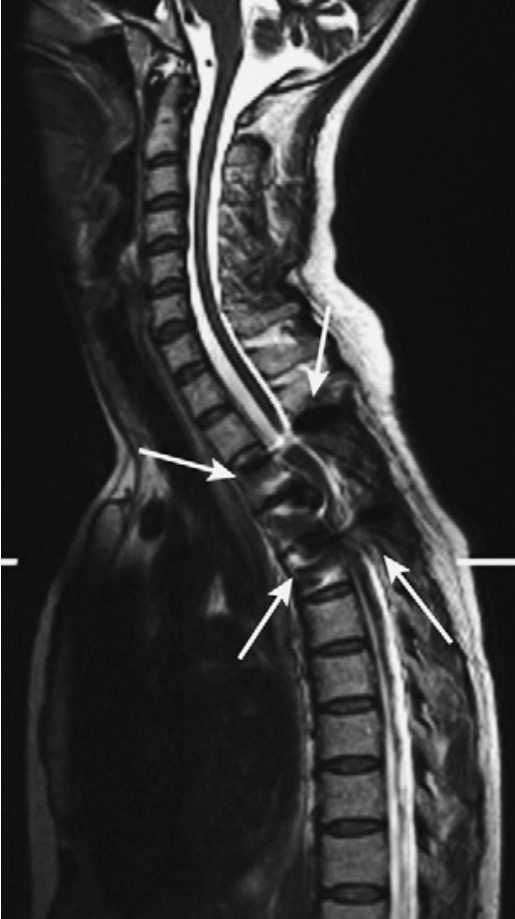

脑脊液流动伪影常易误诊为病变,需与椎管内占位相鉴别。如脊髓背侧脑脊液中可见多个不连续的低信号区,在不同序列成像中表现不同,有时可通过梯度回波 T2 加权像消除此伪影。

蓝色箭头所指的是由脊髓腔内脑脊液流动所形成的流动伪影,白色箭头所指的则是截断伪影。蓝色和白色箭头所呈现的征象均属于伪影,椎管和脊髓实际上是正常的,而星号区域为 L1 椎体血管瘤。